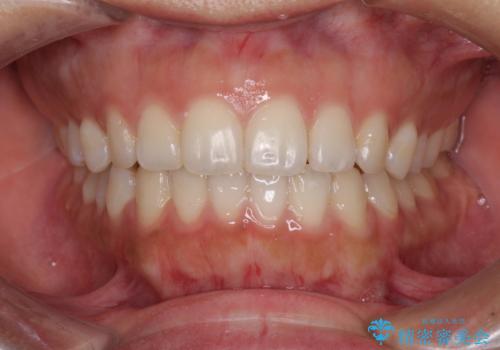

話しにくいオープンバイト ワイヤー装置による抜歯矯正治療

- 前歯のオープンバイトを気にして来院された患者様です。

上下前歯の前後位置が大きくずれていたため、上顎左右第一小臼歯2本を抜歯してワイヤー装置による矯正治療を行うこととしました。

オープンバイトの原因は舌の突出癖であり、癖が改善されないと治療経過に影響を及ぼすため、舌のトレーニングを指示しました。

なかなか癖が改善されず、トレーニングも断続的に行ったため、治療期間は長期化しました。